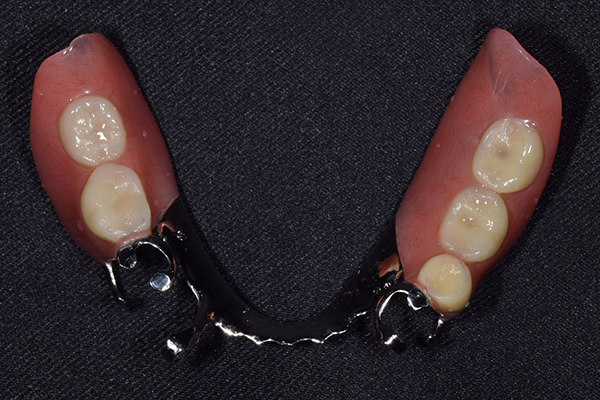

ケース3(インプラントを用いた部分入れ歯)

右上と左下の歯がない方です。 上の入れ歯の安定が悪く、作り直したいとのことでいらっしゃいました。 今お使いの上の入れ歯を見てみると、口蓋部分が抜けており、安定性に欠ける構造になっていました。この入れ歯はノンメタルクラスプデンチャーといって、金属のバネを使用しない 入れ歯になります。これは見た目は良いのですが、歯への負担が大きいことと、入れ歯自体がやわらかいため、噛むには不便なことがあります。

入れ歯は極力薄くするために金属を使用しました。しっかり噛める様にするため、ノンメタルクラスプデンチャーにはしませんでした。

上の入れ歯(表)

上の入れ歯(裏)

下の入れ歯

入れ歯を入れた状態のお口の中の写真です。バネも極力目立たないように作成しています。

年齢 70代・女性

主訴 上の入れ歯の安定が悪く、作り直したい

治療期間 5ヶ月

治療費 .診査診断:55,000円

.インプラント埋入:165,000円

.アバットメント:33,000円

.義歯:330,000円

治療方針 右片側のみ奥歯がない方です。

この様な場合入れ歯は反対側に維持を求めるため、大きな入れ歯になりがちです。

そのため違和感が強いことがおおいです。

また、片側だけないですので、安定もむずかしくなります。

そこで、安定をよくするために、右の奥歯の位置にインプラントをいれて、義歯が揺れない様にすることにしました。

治療内容 レントゲンをみて最低限の長さのインプラントを右上の奥歯の位置に埋入しました。インプラントと骨の結合(オッセオインテグレーション)と歯肉の治癒を待ち、アバットメントをいれて型取りをして、入れ歯を作成しました。極力薄くするために、金属をもちいた入れ歯にしました。

特記事項 インプラントは必ず成功するというものではありません。 また治癒も人それぞれで、長くかかることもあります。 入れ歯を入れ終わったあとも、アバットメントが緩んできたり、入れ歯が歯ぐきにあたって痛いところもでてきますので、調整は必要になります。